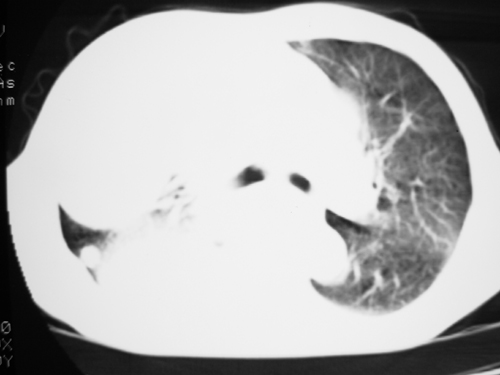

以下是引用yangyudong333在2008-4-29 5:46:00的发言:[br]1左上叶结节呈分叶状,边缘毛刺,考虑肺癌并纵隔淋巴结转移可能性大,结核待排,[br] [br]2右侧多发包裹性胸腔积液

以下是引用zsl6918在2008-4-29 9:15:00的发言:[br]右侧包裹性积液穿刺术后改变,肺内多发结节不除外转移可能。建议查胸水,问病史。